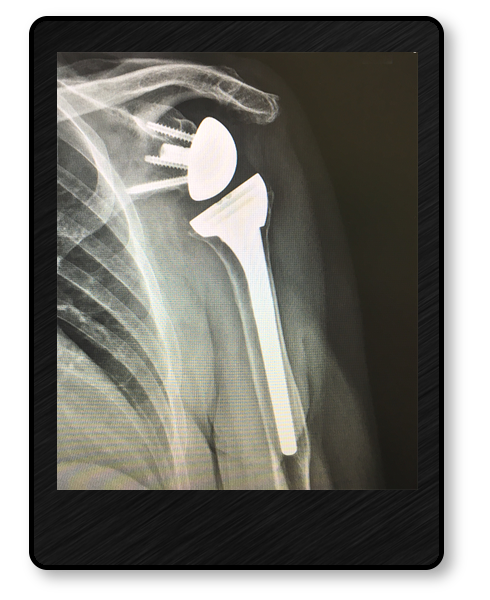

Complex Shoulder Reconstruction

In cases where the cartilage has worn away in the shoulder joint, causing severe pain from arthritis, it is sometimes necessary to perform a Total Shoulder Replacement. Depending on the reason for the arthritis, some patients may need a specialized replacement called a Reverse Total Shoulder replacement. Both are excellent options for restoring patients function while reducing their pain.